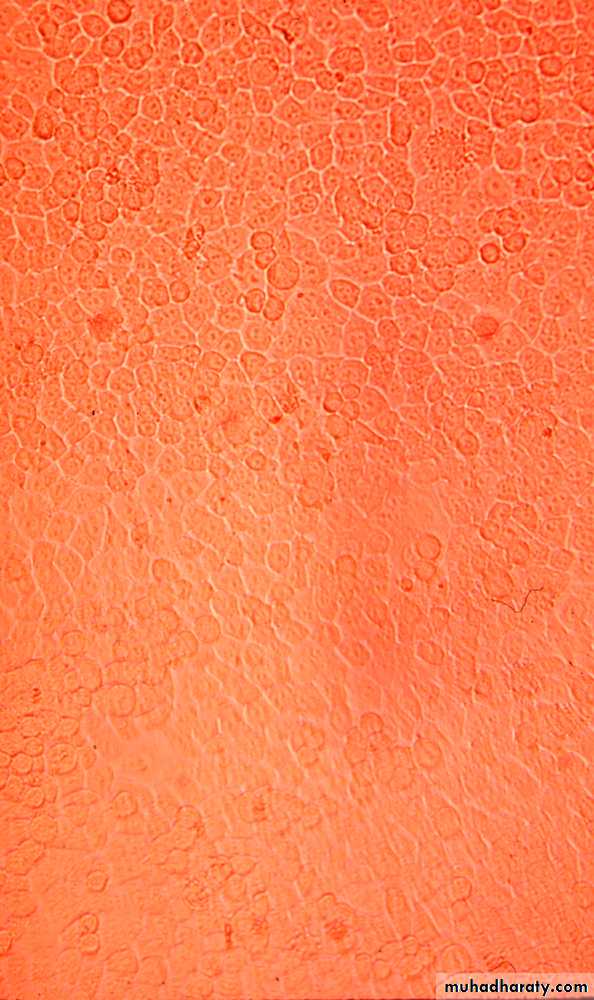

1. Development of cytopathic effects, include cell lysis or necrosis, inclusion bodies formation, giant cell formation, and cytoplasmic vacuolization.2. Appearance of a virus-encoded protein, such as the hemagglutinin of influenza virus.

Detection of Virus-Infected Cells

uninfected

early infection

late infection